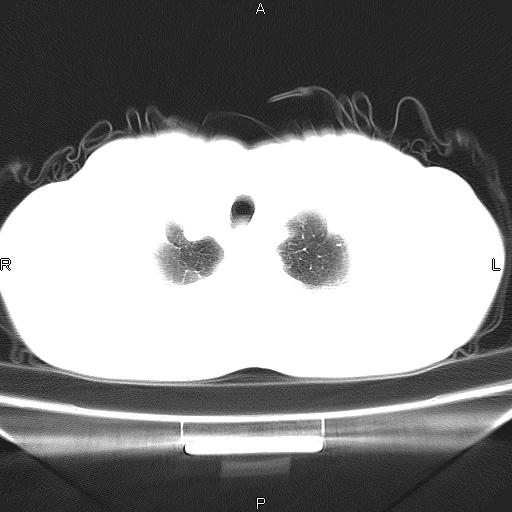

患者,男。50岁。近几日有咳嗽症状,无其他不适,既往病史无,考虑膈疝。请前辈们看看指导指导。

膈膨升,左下肺通气不良,膈肌好像还完整。

考虑左侧膈疝。

左侧膈疝。

符合隔膨升,膈肌较完整。